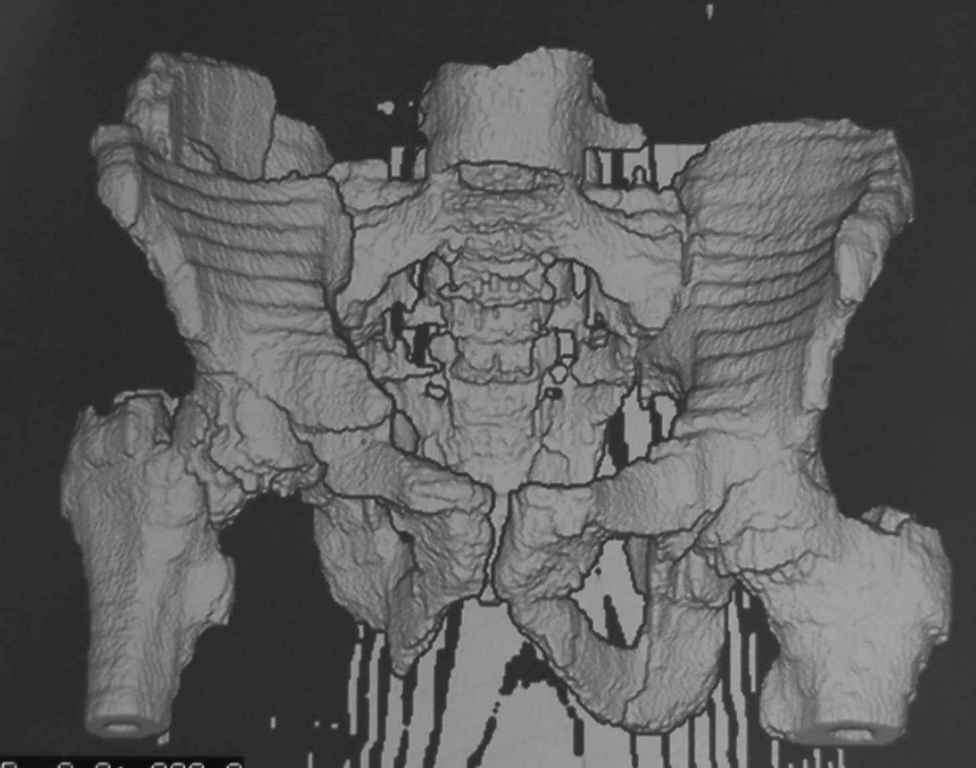

Уважаемый Алексей, на представленных Вами снимках имеется вертикально-нестабильное повреждение тазового кольца без повреждения вертлужной впадины. Учитывая это, а так же растущий возраст ребенка я бы выбрал аппарат внешней фиксации в виде кольцевой опоры, т.к. не смотря на оскольчатый перелом крыла в переднем отделе можно ввести минимум 2 стержня + 1-2 надвертлужно. Этого будет достаточно чтобы "зацепится", выполнить репозицию и дальнейшую фиксацию. Перелом шейки по моему лучше прооперировать 3 канюлированными винтами по АО.

Таз - подвздошным и падлобковым доступом раздельные рекострукционные пластины 4 штуки. Сплошную пластину как у взрослых нельзя (из-за роста придется доставать)

1 аппаратом сложно управлять при оскольчатом переломе крыла

2 для будущей мамы желателен максимально восстановленный таз